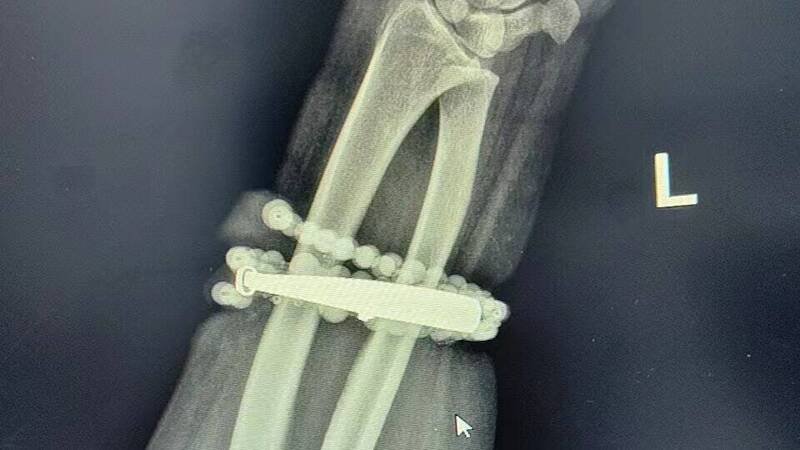

手镯和串珠链「长」进肉里。(图:福建卫生报)

中国福建省宁德市近日出现1起惊悚医疗案例,1名33岁龚姓女子因手腕上的银手镯与串珠,长达10年未曾取下,随著体重增加,饰品竟不知不觉中「长进肉里」,导致严重感染、红肿化脓。医师警告,若再延误就医,不仅可能需要截肢,甚至恐引发败血症危及性命。

根据《福建卫生报》报导,龚女10年前戴上银手镯与串珠后,几乎从未摘下。这些年来,随著她的体重增加,她发现手腕越来越紧,但一开始并未放在心上。直到近半年,她戴著饰品的手腕皮肤,反复出现红肿、搔痒,她以为只是普通皮肤炎,便自行涂抹药膏处理。

岂料,约2周前,她的情况急转直下,手腕不仅剧痛,更渗出脓液。她仔细一看才惊觉,有部分手镯已「嵌入肉中」,完全取不下来,于是立即就医。

医师检查后指出,这是首饰长期压迫摩擦,加上细菌感染,造成的慢性发炎与肉芽组织增生。增生的组织已形成1圈「肉环」,紧紧包裹住饰品,并散发恶臭。

由于感染严重,医疗团队决定采取手术处理。主刀医师形容,手术过程如同「考古挖掘」,必须沿著手镯与串珠的形状,小心翼翼地将被肉芽组织「吞噬」的部分分离出来,避免伤及血管与神经。历经约1小时的精细操作,手术团队才成功取出已失去光泽的首饰。术后龚女感激地表示:「真的太谢谢医生了,我以为我的手保不住了!」

对此,医师提醒民众,长期佩戴饰品应定期清洁,若体重增加或出现水肿导致饰品紧绷,应及早移除。若佩戴部位出现红肿、疼痛等情况,应立即取下并就医。

中国福建一名33岁龚姓女子戴银手环和串珠长达10年未摘下,竟长进肉里,差点要截肢。(图翻摄自微博)